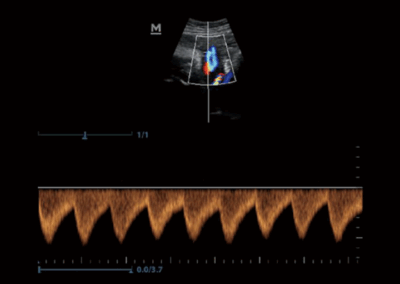

Z50

Sistema de diagnóstico ecográfico.

Con la combinación definitiva de alto rendimiento, aplicaciones clínicas integrales y diseño integrado, el Z50 lo ayudará a responder de manera más rápida y eficaz. El cambio de un sistema en blanco y negro a un sistema Doppler a color altamente eficiente ahora se ha vuelto más fácil y simple que nunca, lo que hace posible ir más allá de los límites y trascender lo habitual cuando se trata de la atención de los pacientes.